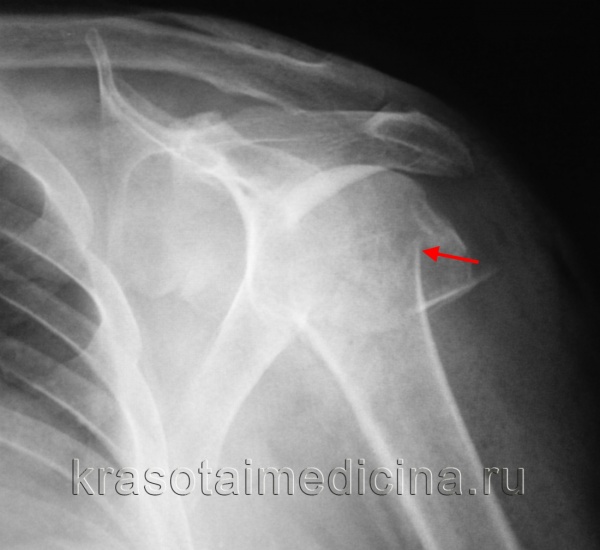

Рентгенограмма при переломе диафиза плечевой кости

(Слева) На боковой и передне-задней рентгенограммах правого плечевого сустава у женщины 62 лет с болью и деформацией после падения с высоты тела виден перелом средней трети диафиза плечевой кости с варусным отклонением >30°. Кроме того, она не могла разогнуть запястье. Пацинтке проведена успешная закрытая репозиция под анестезией, проведенной в связи с парезом лучевого нерва и варусным отклонением.

(Справа) На передне-задней рентгенограмме виден оскольчатый спиральный перелом плечевой кости. Перелом хорошо сросся в гильзовой повязке.

2. Рентгенография при переломе диафиза плечевой кости:

• Линейное просветление на передне-задней или боковой рентгенограммах:

о Часто варусное отклонение